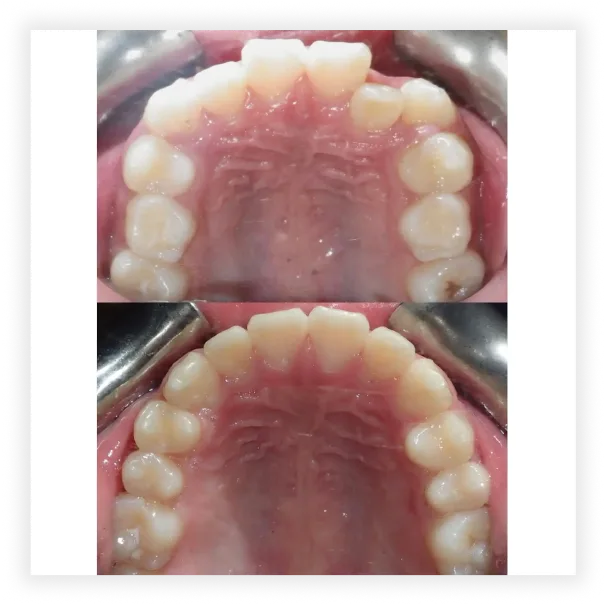

Take a look at some of our cases and successful transformations below.

Case #1

Final Photos